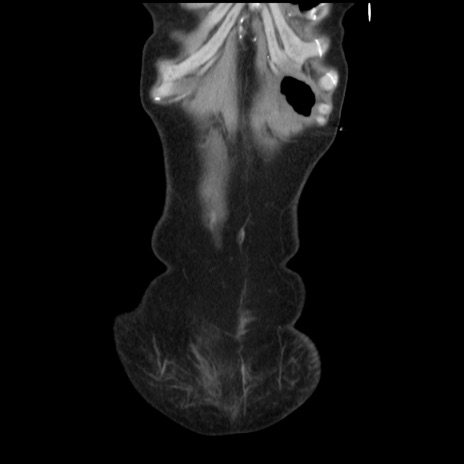

症例32(冠状断像)

矢状断像